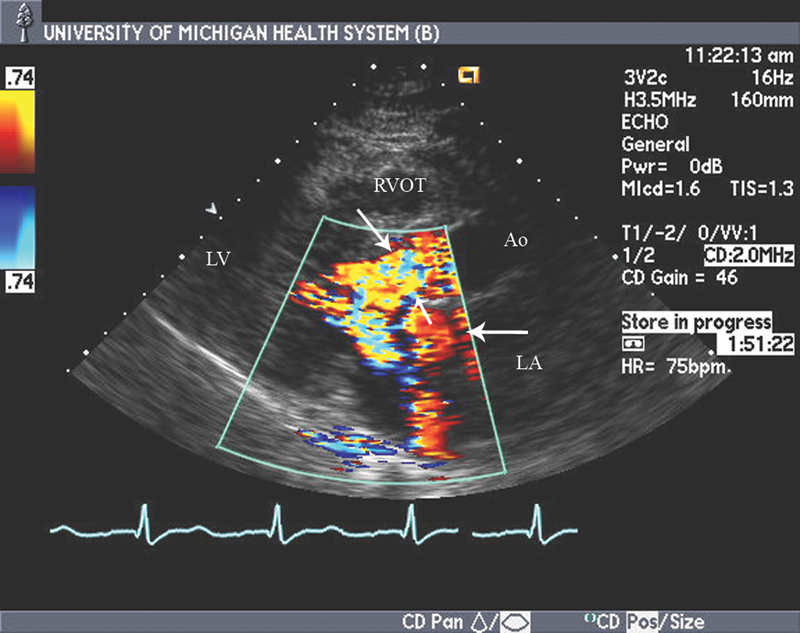

فحوصات تشخيصية لبعض امراض القلب والشرايين التاجية